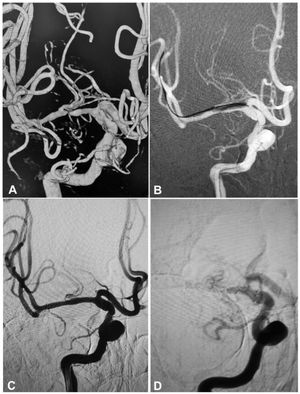

A 54-year-old man had an atherosclerotic stenosis (88%) at the M1 segment of the right middle cerebral artery treated with angioplasty and stenting of the Low-Profile Visualized Intraluminal Support (LVIS) stent. (A) The stenosis was shown at the M1 segment. (B) A balloon was used to dilate the stenosis before stenting. (C) At the end of the stenting with a LVIS stent (3.5mm×15mm), the stenotic segment was almost restored to the normal diameter. (D) At 6-month follow-up, the stented segment of artery was totally occluded with no symptoms.